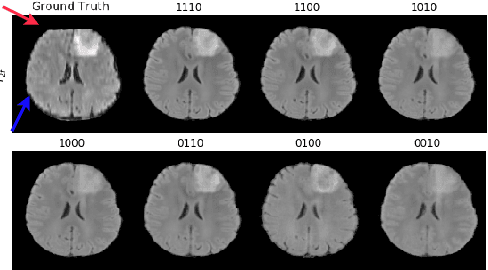

Abstract:Magnetic resonance imaging (MRI) is being increasingly utilized to assess, diagnose, and plan treatment for a variety of diseases. The ability to visualize tissue in varied contrasts in the form of MR pulse sequences in a single scan provides valuable insights to physicians, as well as enabling automated systems performing downstream analysis. However many issues like prohibitive scan time, image corruption, different acquisition protocols, or allergies to certain contrast materials may hinder the process of acquiring multiple sequences for a patient. This poses challenges to both physicians and automated systems since complementary information provided by the missing sequences is lost. In this paper, we propose a variant of generative adversarial network (GAN) capable of leveraging redundant information contained within multiple available sequences in order to generate one or more missing sequences for a patient scan. The proposed network is designed as a multi-input, multi-output network which combines information from all the available pulse sequences, implicitly infers which sequences are missing, and synthesizes the missing ones in a single forward pass. We demonstrate and validate our method on two brain MRI datasets each with four sequences, and show the applicability of the proposed method in simultaneously synthesizing all missing sequences in any possible scenario where either one, two, or three of the four sequences may be missing. We compare our approach with competing unimodal and multi-modal methods, and show that we outperform both quantitatively and qualitatively.